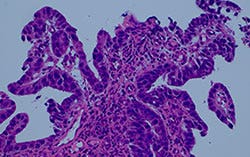

Figure 4: Comparison of a halogen lamp with filter versus a generic LED and a True Color LED

Comparison of halogen lamp + filter and True Color LED